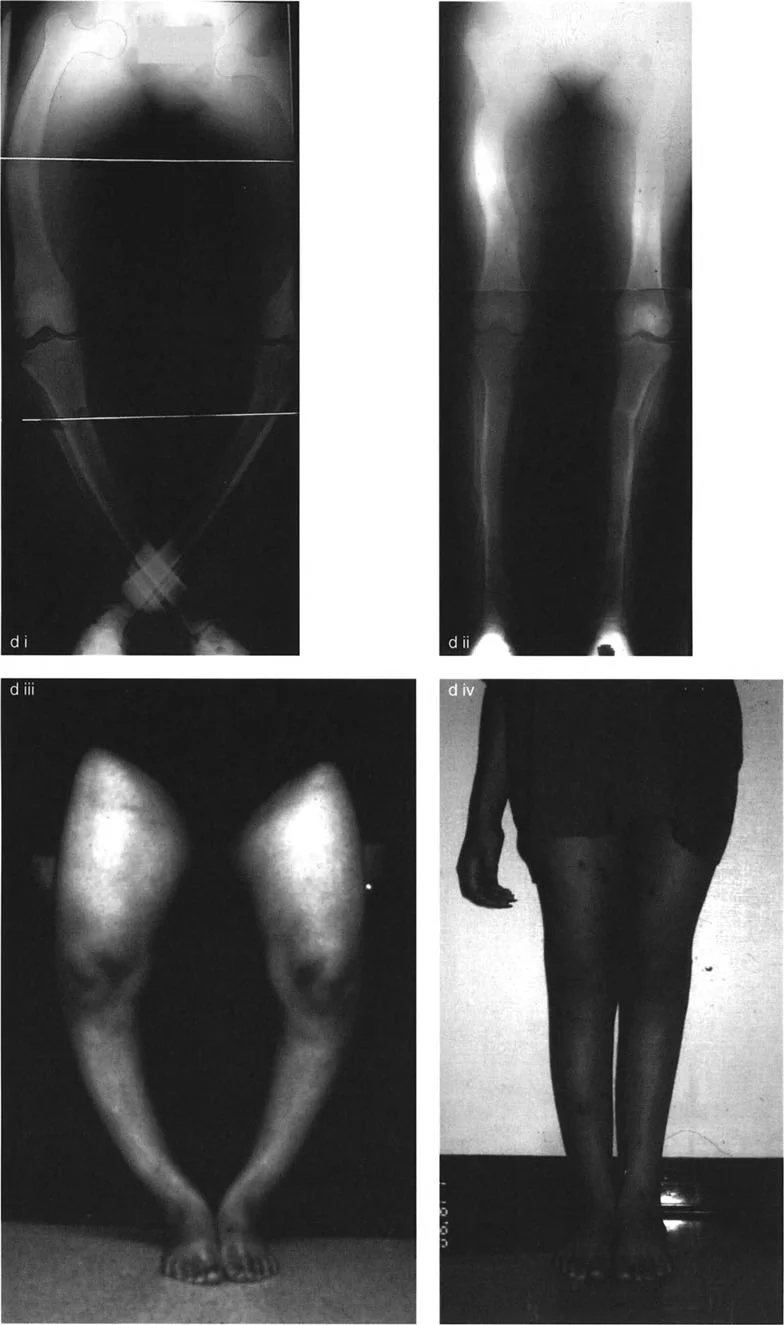

الحل أحادي المستوى (Uniapical Solution)

في هذا النهج، يتجاهل الجراح الانحناءات الفردية المتعددة وبدلاً من ذلك يجد القمة المُحللة للتشوه بأكمله.

• التقنية: تُرسَم خطوط المحور الميكانيكي القريب (PMA) والبعيد (DMA). في التشوه التقوسي متعدد الرؤوس، ستتقاطع هذه الخطوط بعيدًا عن العظم (إلى الناحية الوحشية أو الإنسية لمنتصف الجسم). هذه هي نقطة CORA المُحللة.

• التصحيح: يُعاد محاذاة المحور الميكانيكي بقطع عظم واحد. على سبيل المثال، تصحيح زاوي بمقدار 35 درجة حول نقطة CORA المُحللة لعظم الفخذ وتصحيح زاوي بمقدار 37 درجة حول نقطة CORA المُحللة لعظم الساق.

• النتيجة: تُعاد توجيهات مفاصل الكاحل والركبة والورك إلى طبيعتها. يمر المحور الميكانيكي بشكل مثالي عبر مركز الركبة. ومع ذلك، نظرًا لأن قطع العظم تم إجراؤه على مستوى واحد لتصحيح تقوس متعدد المستويات، فإن المحور التشريحي يُصبح متعرجًا (zigzagged). يبدو العظم متعرجًا جسديًا أو "على شكل حرف Z" في الأشعة السينية.

الحل متعدد المستويات (Multiapical Solution)

في هذا النهج، يُعالج الجراح كل انحناء على حدة.

• التقنية: يُرسَم خط محور وسطي عبر جسم العظم، يتقاطع مع PMA و DMA لتحديد نقطتي CORA منفصلتين في كل عظم.

• التصحيح: يُعاد محاذاة المحور الميكانيكي بقطع عظمين منفصلين لكل عظم. على سبيل المثال، تصحيح 20 درجة و 15 درجة في عظم الفخذ، وتصحيح 21 درجة و 16 درجة في عظم الساق.

• النتيجة: تُعاد توجيهات مفصلي الورك والركبة إلى طبيعتها. علاوة على ذلك، تُعاد محاذاة المحاور التشريحية بشكل مثالي، ويظهر محيط العظم طبيعيًا من الناحية التشريحية.

يُحدد الأستاذ الدكتور محمد هطيف، بناءً على خبرته الواسعة في صنعاء، النهج الأنسب لكل مريض، مع الأخذ في الاعتبار شدة التشوه، عمر المريض، وتوقعاته، لضمان أفضل نتيجة وظيفية وجمالية.